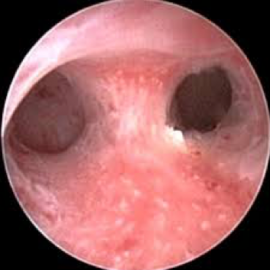

لتشخيص أسباب فشل التعشيش والإجهاضات المتكررة وأمراض جوف الرحم مثل البوليبات والحجب والالتصاقات باطن الرحمية التي تعيق الحمل واستمراره إضافة إلى أمراض بطانة الرحم مع إمكانية إجراء التداخل الجراحي العلاجي المناسب تنظيرياً وبنفس المرحلة.

وقد تم حديثاً إدخال Office Hysteroscopyالمتميز بقطر صغير بحيث يمكن إجراء التداخل الجراحي دون توسيع عنق الرحم وبالتالي دون الحاجة للتخدير العام في كثير من الحالات.